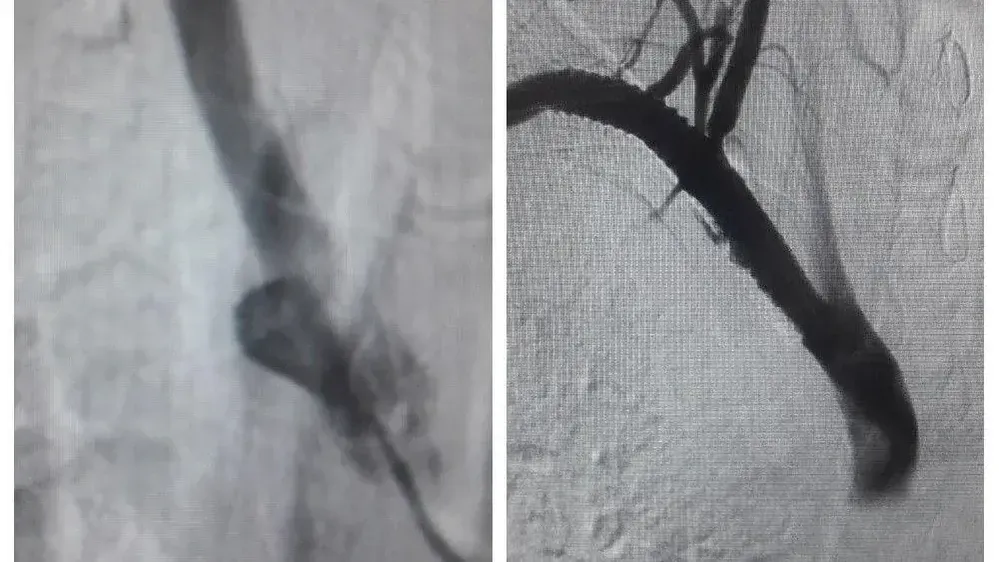

В результате обследований врачи выявили у него тромб, который полностью закупорил подключичную артерию. Это один из самых больших сосудов организма, снабжающий верхнюю часть правой половины туловища, в том числе мозг. Ситуация грозила развитием инсульта, потерей конечности и возможным летальным исходом.

Пациенту провели экстренную операцию — тромбоэкстракцию, удалили тромб длиною 5 см и диаметром около 8 мм, а затем выполнили стентирование сосуда. Сложность вмешательства заключалась в нетипичном расположении артерий у пациента, а также в массивности тромба. Операция проведена эндоваскулярно с помощью ангиографической установки. Преимущество данной методики заключается в том, что она выполняется без разрезов и наркоза.